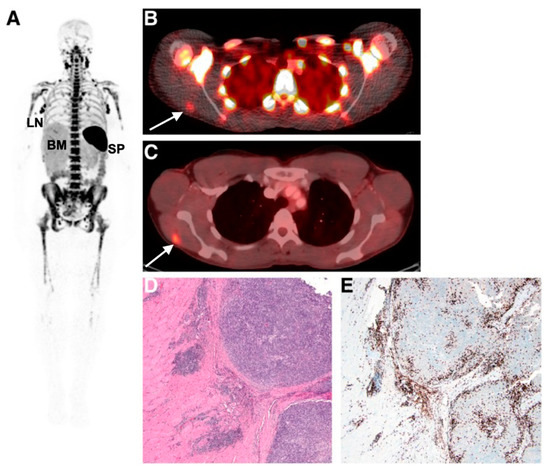

Figure 4.

Imaging human T-cell tumour infiltration using [89Zr]Zr-IAB22M2C, a radiolabelled minibody targeting CD8. (A) Normal splenic, bone marrow, and lymph node uptake of the tracer were observed. Uptake of (B) [89Zr]Zr-IAB22M2C and (C) [18F]FDG in a melanoma metastasis in the deltoid muscle of a patient was histologically confirmed as high CD8+ T-cell infiltration (D,E). Figure reproduced from [87].